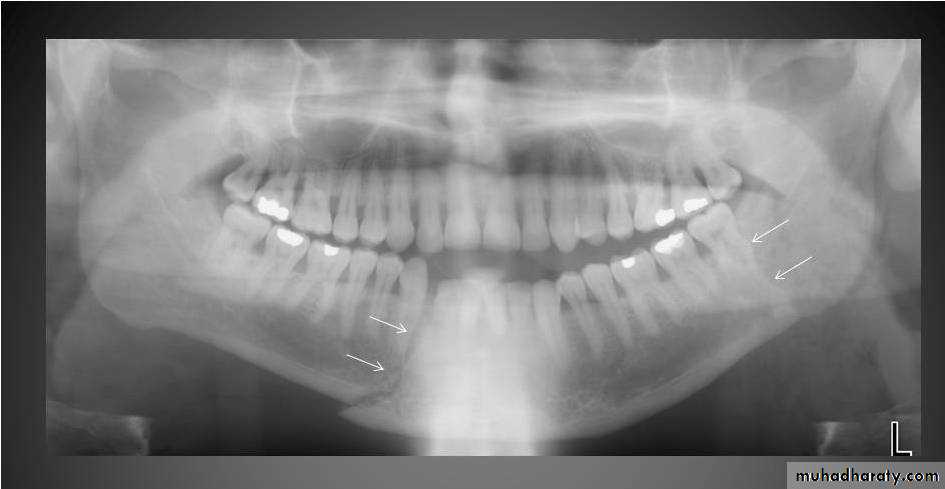

Bitewing radiograph. This radiograph shows (1) large occlusal caries, (2) radiolucent lines or mach band effect (an optical illusion caused by overlapped enamel), (3) interproximal caries, and

(4) cervical burnout